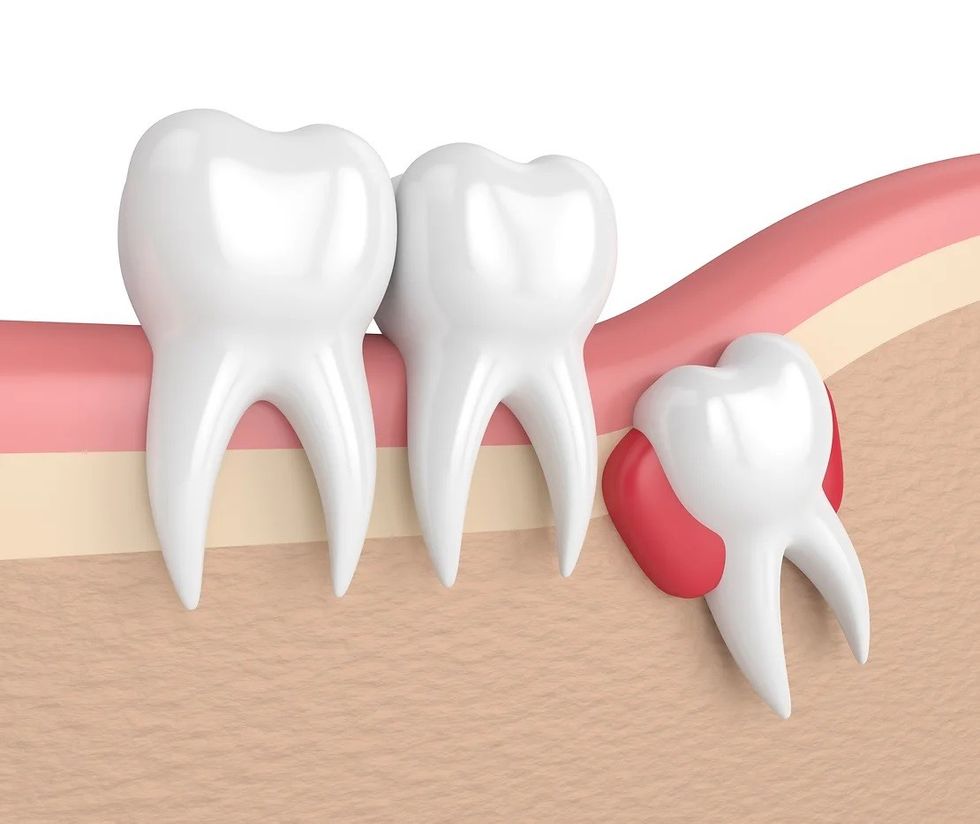

Problemi më i shpeshtë klinik që shohim është perikoroniti, (një infeksion i lokalizuar). Pa hapësirë të mjaftueshme për eruptim të plotë të dhëmbit të pjekurisë, indi i mishit të dhëmbëve rreth dhëmbit të pjekurisë mund të irritohet dhe infektohet, duke rezultuar në dhimbje të përsëritura, ënjtje dhe probleme me përtypjen dhe/ose gëlltitjen.

3. Dendësi të dhëmbëve

Dhëmballët e pjekurisë të impaktuara mund të kontribuojnë në përkeqësimin e grumbullimit të dhëmbëve tuaj. Kjo vërehet më së shumti me dhëmbët e përparmë, kryesisht me dhëmbët e përparmë të poshtëm dhe më së shpeshti vërehet pasi një pacient ka pasur proteza fikse për drejtim të dhëmbëve.

4. Dëmtimi i dhëmbëve ngjitur

Nëse nuk ka hapësirë të mjaftueshme për të pastruar rreth dhëmbit të pjekurisë, dhëmbi që gjendet para tij, molari i dytë, mund të ndikohet negativisht duke rezultuar në sëmundje të mishrave të dhëmbëve, humbje kockash rreth dhëmbit dhe/ose prishje.